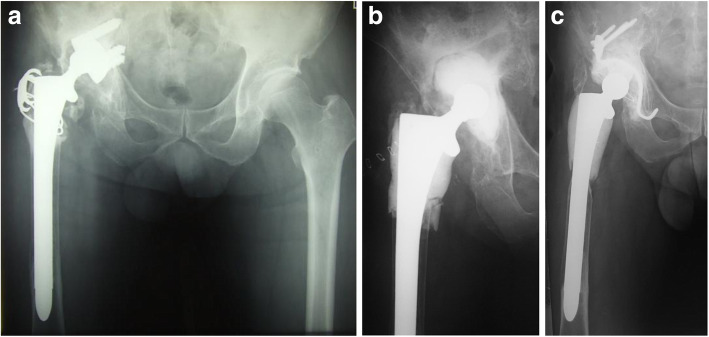

Case 1: A 65-year-old man who developed late infection 3 years after revision THA. Synovial fluid aspirate and intraoperative culture were both positive for Staph. Epidermidis (Fig. 1a). The fully-porous coated long stem was retained and we resected all the infected proximal femur (Fig. 1b). No signs of recurrence of infection were observed during a period of 158 months after the second-stage reconstruction (Fig. 1c).

Fig. 1.

a A 65-year-old man developed late infection 3 years after revision THA. b The fully-porous coated long stem was retained and all the infected proximal femur was resected. Articulating cement spacer was made in the acetabular defect. c No signs of recurrence of infection were observed 158 months after the second-stage reconstruction

Case 2: A 52-year-old woman developed deep MRSA infection after THA that was performed 4 years after pelvic osteotomy (Fig. 2a). Despite four repeated irrigation and debridement procedures, the previous surgeon failed to achieve suppression of infection and the patient was referred to our department having developed multiple chronic sinus tracts in her thigh (Fig. 2b). In this patient, 12 hydroxyapatite spacers (containing 1 g of VCM) (BONECERAM-P; Olympus Terumo Biomaterials Co., Tokyo) were used in addition to ALAC (containing 2 g of VCM) (Fig. 2c). The tissue cultures at the second-stage surgery were all negative. Ninety-four months after the second-stage reconstruction, the patient had a good postoperative course with no signs of recurrence of infection (Fig. 2d).

Fig. 2.

a A 52-year-old woman developed deep MRSA infection after THA. b The patient was referred to our department after four repeated irrigation and debridement procedures having developed multiple chronic sinus tracts in her thigh. c Hydroxyapatite spacers in addition to articulating cement spacer were used to contain antibiotics in this patient. d No signs of recurrence of infection were observed 94 months after the second-stage reconstruction